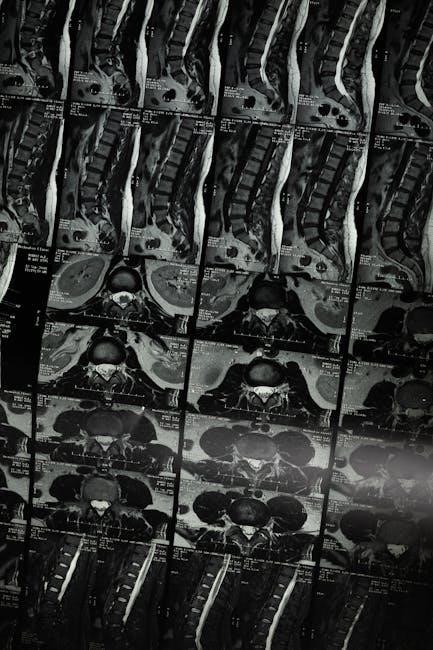

Spinal stenosis isn’t a disease itself, but rather a condition arising from the narrowing of spaces within your spine․ This narrowing can put pressure on the spinal cord and nerves, leading to a variety of symptoms․ Understanding the mechanics of this compression is crucial when approaching spinal stenosis exercises․

Spinal stenosis refers to the narrowing of the spinal canal, the space within your vertebrae that houses the spinal cord and nerves․ This narrowing can occur in the neck (cervical stenosis) or the lower back (lumbar stenosis)․ As the space decreases, these vital structures can become compressed, leading to pain, numbness, and weakness․